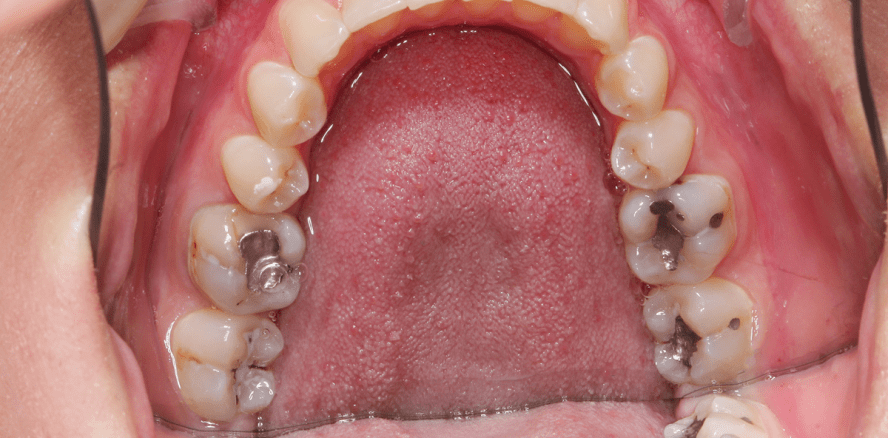

Trotz harscher Kritik befinden sich immer noch rund 10’000 Kilo Amalgam in den Mündern der Schweizer Bevölkerung. Ein generelles Verbot nach dem Vorbild von Schweden wurde 2009 abgelehnt. Zwar sind die im Amalgam enthaltenen Giftstoffe extrem gering, Kritiker schlagen dennoch Alarm.

2009 setzte Schweden ein Zeichen und verbot die Verwendung von Quecksilber und somit auch den Gebrauch von Amalgam. Grund waren die gesundheitlichen Beeinträchtigungen, die man dem Füllungsmaterial nachsagt. Im selben Jahr wollte die Schweiz nachziehen, allerdings wurde dies vom Bundesrat abgelehnt, da es „aus Gründen des Gesundheitsschutzes nicht zu rechtfertigen“ sei. Amalgamkritiker sehen das natürlich anders und fordern aufgrund der toxischen Stoffe, die zu gesundheitlichen Schäden unter anderem in den Nieren und im Nervensystem führen können, ein generelles Verbot. Von der Weltgesundheitsorganisation (WHO) gibt es vorsichtige Entwarnung, die Amalgam als ungefährlich einstuft. Die Menge an Quecksilber, die durch Nahrung, Atmung oder eben solche Füllungen aufgenommen wird, sei zu gering, um wirklichen Schaden im menschlichen Körper anrichten zu können. Insgesamt verringert sich die Menge an Amalgamfüllungen in der Schweiz jedes Jahr aber dennoch um bis zu 350 Kilo, da sich immer mehr Patienten für die optisch ansprechenderen Kunststofflösungen entscheiden. Da das von Schweden angekurbelte EU-weite Amalgam-Verbot noch keinen Anklang gefunden hat, wird sich auch in der Schweiz erst einmal nichts Konkretes hinsichtlich der Verwendung des Füllungsmaterials ändern.